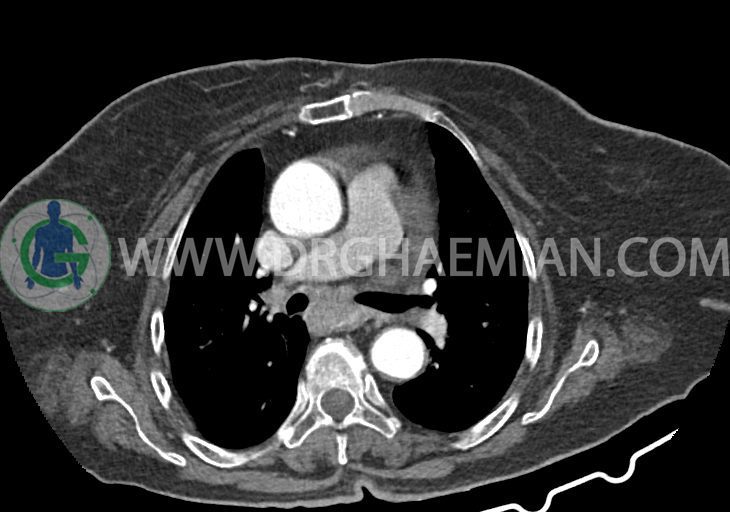

در سی تی اسکن اسپیرال ریه و مدیاستن – شکم و لگن با و بدون کنتراست خوراکی و وریدی (مولتی دیدکتور 16 با مقاطع ظریف و بازسازی های ساژیتال و کرونال):

تراشه و برونش های اصلی نرمال اند. پنومونی، پلورال افیوژن، جابجایی محتویات مدیاستن ، فیبروز ریوی و Collection مشهود نیست.

–کاردیومگالی همراه با pericardial effusion خفیف

–آئورت صعودی دیلاته به قطر 38mm

–تغییرات دژنراتیو مهره های توراسیک و اسکولیوز توراکولومبار